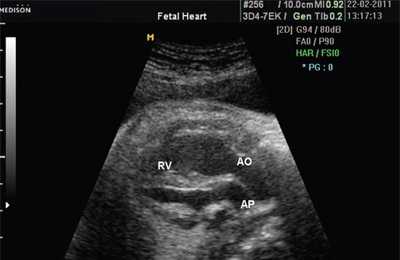

В равной степени это относится к дефекту межжелудочковой перегородки (рис. 6), простой форме транспозиции магистральных сосудов (рис. 7, 8), транспозиции магистральных сосудов с дефектом межжелудочковой перегородки (синдром Тауссиг - Бинга) (рис. 9), общему желудочку (рис. 10), общему артериальному стволу (рис. 10), двойному отхождению сосудов от одного из желудочков сердца (рис. 11).

Рис. 10. Общий желудочек с отхождением TRUNCUS ARTERIOSUS. Стрелками показано разделение TRUNCUS ARTERIOSUS на аорту и ствол легочной артерии.

Рис. 11. Двойное отхождение магистральных сосудов от левого желудочка. Длинная ось сердца. Магистральные сосуды инвертированы и отходят от левого желудочка. Аорта расположена "верхом" над дефектом межжелудочковой перегородки (стрелка).

LV и RV - левый и правый желудочек, АР - легочная артерия, АО - аорта, VSD - дефект межжелудочковой перегородки.